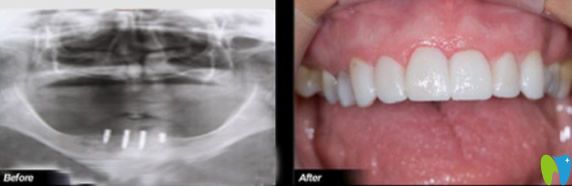

深圳歡樂口腔堅持口腔治療、四手規(guī)范操作、“一人一機”無菌消毒的標準化醫(yī)療規(guī)范,廣泛應(yīng)用3D打印、數(shù)字引導種植牙、顯微鏡下超薄美容牙、口腔數(shù)字化CT掃描等主流的全數(shù)字化新技術(shù)、新方法,達到了良好的治療,并得到了患者的普遍贊譽。下圖是真人種植牙,大家覺得深圳歡樂口腔怎么樣?

歡樂口腔種植牙